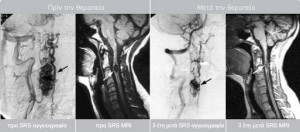

Η επιτυχία που παρατηρείται στην ακτινοχειρουργική αντιμετώπιση των αγγειακών δυσπλασιών του εγκεφάλου προβλέπεται να επαναληφθεί στην σπονδυλική στήλη και άλλα σημεία του σώματος.

Το κέντρο μας διαθέτει μεγάλη εμπειρία στην αντιμετώπιση αγγειακών δυσπλασιών και σηραγγωδών αιμαγγειωμάτων.

Έχουμε αντιμετώπιση περισσότερο από 131 ασθενείς με AVM, με ποσοστό εξάλειψης >90% στη διετία. Αναμένεται από τη θεραπεία μείωση του όγκου του AVM κατά 50% με το μέγιστο να καταγράφεται στην τριετία όποτε και αν υπάρχει υπολειπόμενος ιστός και εφόσον κριθεί απαραίτητο να χορηγείται με ασφάλεια συμπληρωματική δόση.